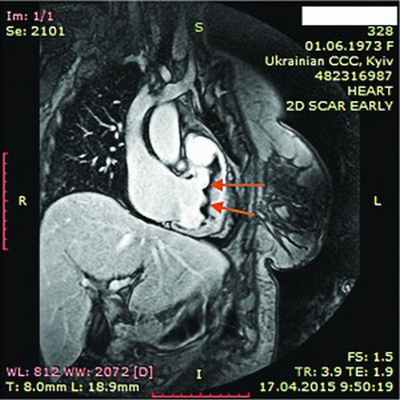

При рентгенологическом обследовании органов грудной клетки обнаруживают кардиомегалию и признаки венозного застоя в легких. Изменения ЭКГ не специфичны. Частые находки – нарушения ритма сердца, особенно фибрилляция предсердий (ФП). В диагностике заболевания основную роль играет эхокардиография (ЭхоКГ), позволяющая обнаружить локальное (реже – диффузное) утолщение верхушки одного или обоих желудочков с вовлечением в патологический процесс хорд, умеренную митральную или трикуспидальную регургитацию, пристеночные, особенно верхушечный, крупные тромбы. Показательным является «рестриктивный тип» ремоделирования сердца и внутрисердечной гемодинамики – очевидное преобладание объема предсердий над объемами желудочков. Систолическая функция, как правило, сохранена, но диагностируется диастолическая дисфункция – рестриктивный тип трансмитрального/транстрикуспидального кровотока. Наиболее информативными методами исследования на сегодняшний день являются магнитно-резонансная томография (МРТ) и мультиспектральная компьютерная томография с контрастированием 14. В литературе описан случай динамического наблюдения за развитием эндокардита Леффлера с серией одновременно производимой позитронно-эмиссионной томографии и контрастированной МРТ с выделением стадий: бессимптомной, острой некротической, симптомной тромботической и фибротической [13]. Выполнение эндомиокардиальной биопсии миокарда правого (ПЖ) или левого (ЛЖ) желудочка позволяет подтвердить или опровергнуть диагноз эндокардита Леффлера.

14.04.2015 г. пациентка была госпитализирована в Национальный научный центр «Институт кардиологии им. Н.Д. Стражеско» в отделение некоронарогенных заболеваний сердца и клинической ревматологии, где был выставлен (подтвержден и уточнен) диагноз: ГЭС. Эндокардит Леффлера с поражением ЛЖ и ПЖ. Массивные пристеночные тромботические наслоения в ПЖ. Апикальный тромб ЛЖ. Мелкие тромбы в ушках обоих предсердий. Синусовая тахикардия. Единичные желудочковые ЭС. Перикардит с небольшим количеством жидкости. СН IIА ст. со сниженной сократительной функцией ЛЖ ІІ ФК по NYHA. Аутоиммунный тиреоидит, эутиреоз. Токсокароз, висцеральная фаза.

ЭхоКГ: Патологические изменения миокарда ПЖ с утолщением стенок до 18 мм. Диффузный гипокинез стенок ЛЖ с дискинезом верхушки – ФВ 44%. В области верхушки ПЖ – наслоения между листками перикарда. Небольшое количество жидкости в полости перикарда – по ЗСЛЖ до 5 мм. Таким образом, в динамике на ЭхоКГ наблюдалось снижение сократительной функции ЛЖ на фоне его гипертрофии и, несмотря на проведенную высокодозовую терапию гормонами, не уменьшилась гипертрофия ПЖ.

В ходе серии динамических МРТ с контрастированием (рис. 7-11) выявлены массивные пристеночные тромботические наслоения в ПЖ, апикальный тромб ЛЖ.